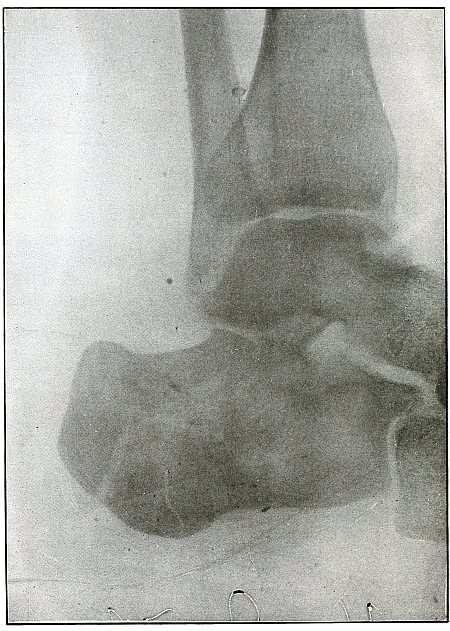

Gunshot fracture, ankle |

154 |

| 73. |

Gunshot wound, heel |

156 |

| 74. |

Gunshot wound, heel |

158 |